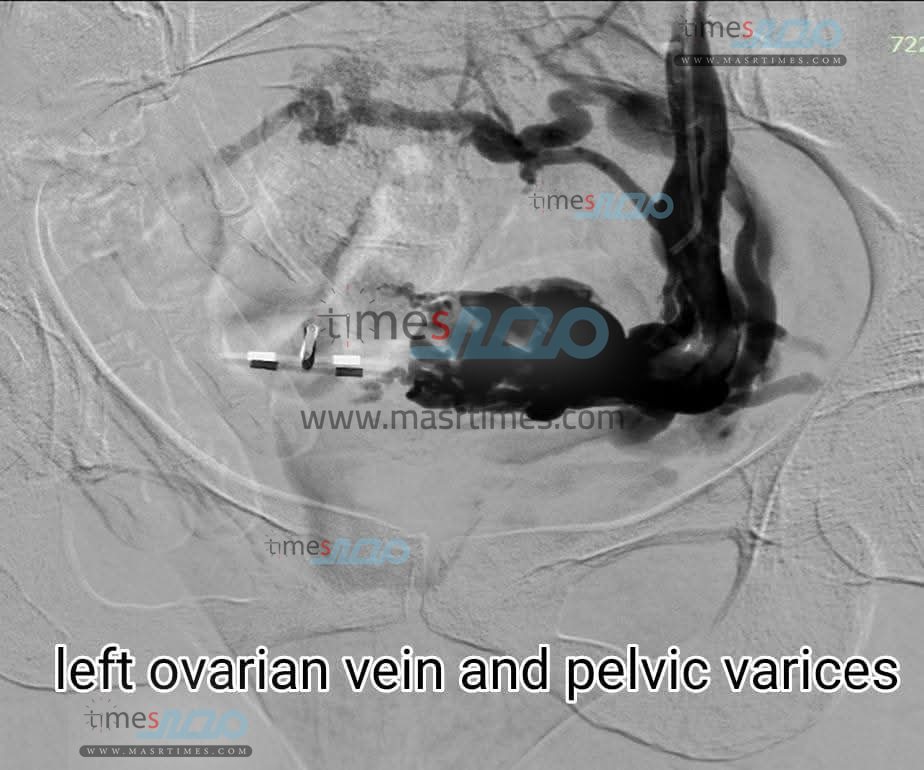

نجح فريق طبي بمستشفيات جامعة المنوفية بقسم الأشعة التشخيصية برئاسة الدكتورة رباب ياسين في تنفيذ تدخل علاجي دقيق لعلاج دوالي الحوض والمبيض الأيسر باستخدام تقنية الأشعة التداخلية الحديثة دون الحاجة إلى تدخل جراحي ويأتي هذا الإجراء ضمن الجهود المستمرة لتطوير الخدمات الطبية وتطبيق أحدث الأساليب العلاجية داخل المستشفيات الجامعية

ومن خلاله أوضح الدكتور محمد النعمانى عميد الكلية أن الحالة كانت تعاني من آلام مزمنة بمنطقة الحوض وبعد الفحوصات الدقيقة تبين وجود دوالي شديدة حول الرحم وارتجاع في وريد المبيض الأيسر وقد تمكن الفريق من غلق الدوالي تمامًا ووقف الارتجاع باستخدام الملفات الحلزونية والمواد اللاصقة للأوردة تحت إرشاد أجهزة القسطرة والموجات فوق الصوتية بما يضمن أعلى درجات الدقة والأمان